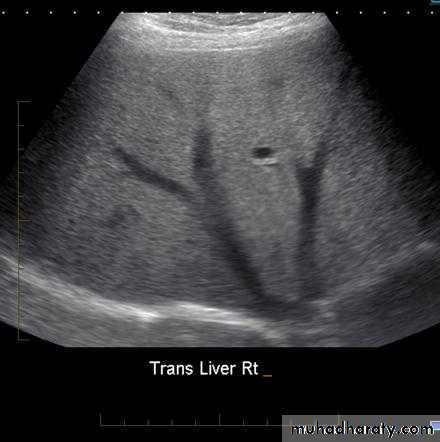

LiverUltrasound : The normal liver parenchyma is of uniform echotexture with portal and hepatic vessels. The normal liver size and shape is variable. Focal masses are noted as alteration of normal echo pattern. They can be divided into cysts, solid or complex masses.

In practice, it is difficult to distinguish benign and malignant lesions unless the mass is clearly a simple cyst.

When multiple masses are seen, metastatic disease is the likely diagnosis. Other differential diagnosis include multiple abscesses and multiple hemangiomas.

US: is the best method for investigation.The patient is asked to fasting 6 hours to prevent GB contraction.

The normal GB has a thin wall< 3 mm, and thickening of wall suggest either acute or chronic cholecystitis. Stones > 2 mm can be identified.

The normal CBD can be visualized in all patients and should not measure>7 mm unless the patient done cholecystectomy when it may be larger.

The lower end of CBD is obscured by bowel gases.

The normal intrahepatic tree is of such smaller caliber to be visualized by US.